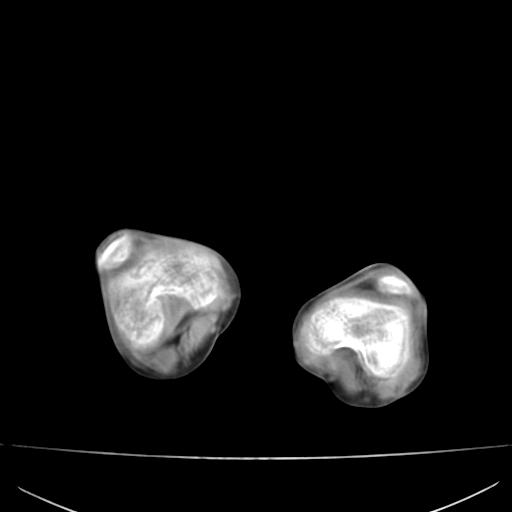

标题: PED0940:M12Y,左股骨下端酸痛畸形 [打印本页]

标题: PED0940:M12Y,左股骨下端酸痛畸形

12岁男孩,左膝关节肿痛8年,近月明显

左右无标记,大部分图像动了,提出诊断困难。

内生骨软骨瘤?

血友性关节病?